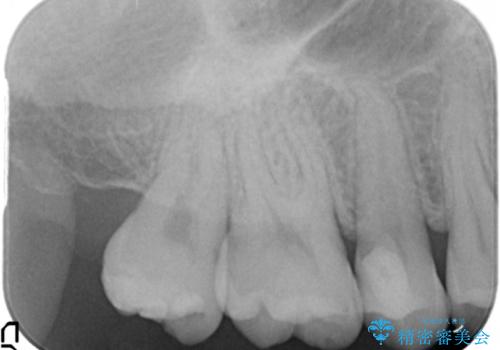

- 上の奥の虫歯をセラミックインレーで修復しました。

奥歯は力がかかるところであるので、保険適応の白い材料は必ず劣化し、2次う蝕(再度虫歯)になる可能性が非常に高いですので全くおすすめできません。

2次う蝕になり、治療を繰り返していると抜髄(神経を取らないといけない)の可能性が高まります。